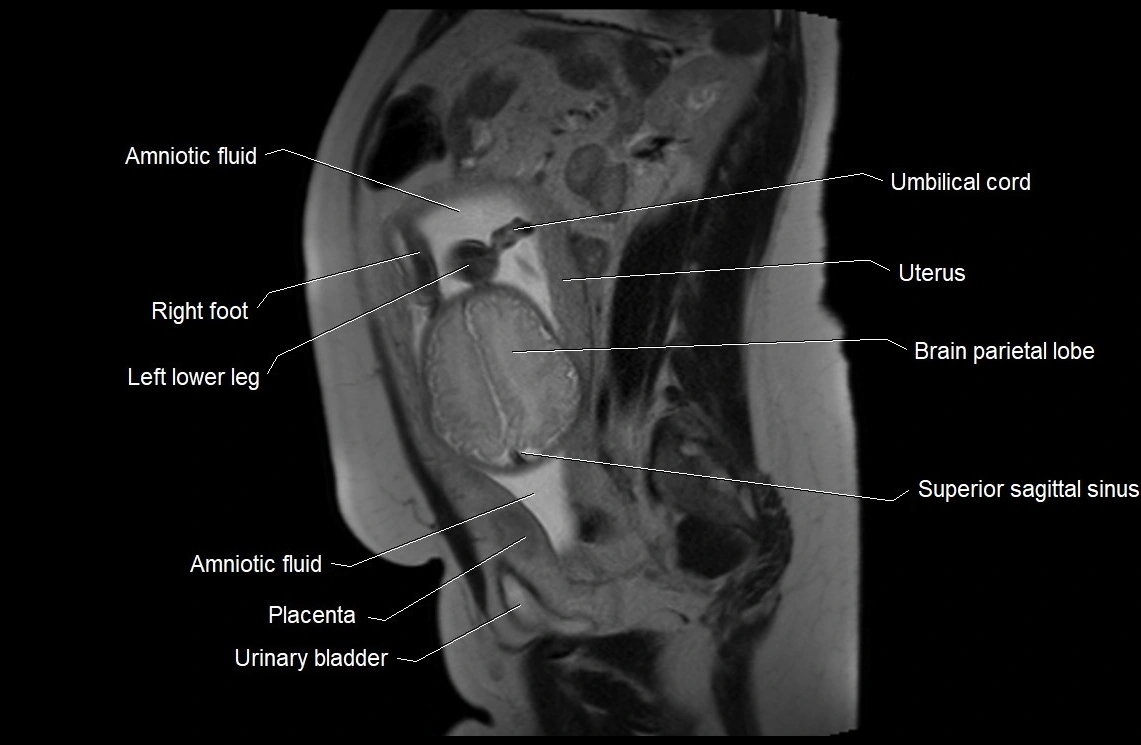

Amniotic fluid is the protective liquid surrounding the fetus within the amniotic sac. It plays an essential role in cushioning the fetus, enabling fetal movement, maintaining temperature stability, and allowing for normal lung and musculoskeletal development.

The volume and composition of amniotic fluid change throughout pregnancy. It is mainly derived from maternal plasma in early pregnancy, while in later stages, it consists largely of fetal urine, lung secretions, and transmembrane exchanges.

MRI Appearance

T2 HASTE (T2 GRE):

• Amniotic fluid shows very bright hyperintense signal

• Provides natural contrast against fetus and placenta

• Small particles (vernix) may appear as scattered hypointense foci within bright fluid

MRI image

image